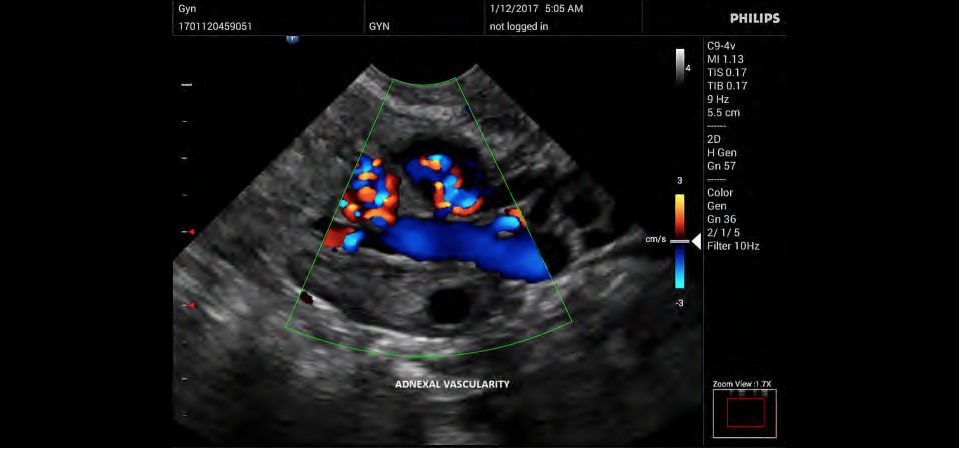

• Конвексный УЗИ датчик Philips C9-4v

• Цветное допплеровское картирование

• Акушерство и гинекология;